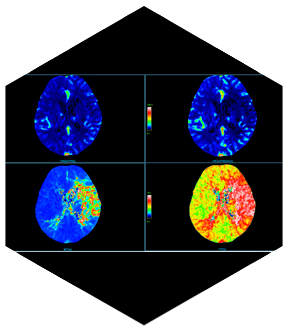

- Интеллектуальная платформа анализа